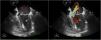

Varón de 82 años, hipertenso y con insuficiencia renal crónica en hemodiálisis, con mala situación basal. Acude por deterioro del estado general de 2 semanas de duración, objetivándose un bloqueo auriculoventricular completo. Ingresa en UCI, estable hemodinámicamente y con oxigenoterapia de bajo flujo. Se realiza ecocardiografía transtorácica, que evidencia una insuficiencia mitral moderada e imagen sugestiva de vegetación en el velo anterior mitral (fig. 1). Hemocultivos positivos para Staphylococcus aureus. La ecocardiografía transesofágica confirma una vegetación de 14×10mm en el velo anterior mitral (A3) y evidencia un pseudoaneurisma (fig. 2,*) en la base del septo interauricular con fistulizaciones múltiples que comunican el tracto de salida del ventrículo izquierdo con ambas aurículas (fig. 3). Dada la situación basal del paciente se desestima para tratamiento quirúrgico.